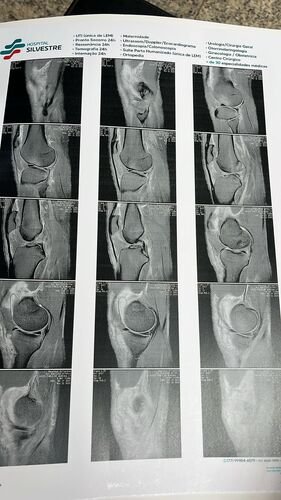

Meu nome é David, no dia 08/11 sofri uma grave lesão no joelho q afetou LCA(ligamento cruzado anterior), LCM(ligamento colateral medial) e menisco, preciso fazer minha cirurgia para voltar a andar e  ter minha rotina de trabalho e estudos ver tudo

Meu nome é David, no dia 08/11 sofri uma grave lesão no joelho q afetou LCA(ligamento cruzado anterior), LCM(ligamento colateral medial) e menisco, preciso fazer minha cirurgia para voltar a andar e  ter minha rotina de trabalho e estudos